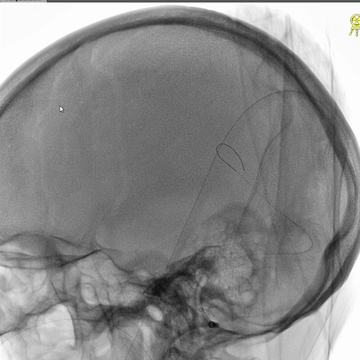

介入治疗后右侧颈动脉造影:上矢状窦、直窦和右侧横窦-乙状窦均见显影,右侧横窦局部狭窄明显。